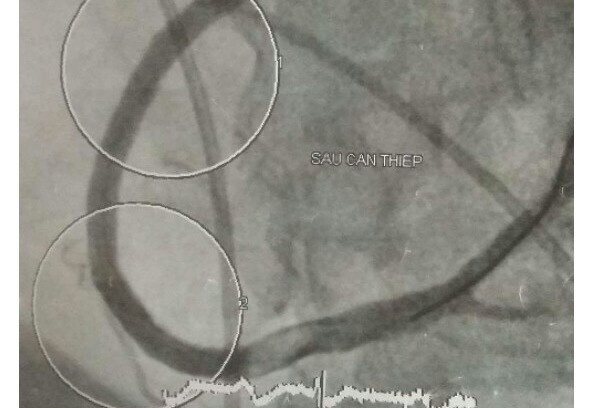

Các BS cho biết, sau khi tiến hành hội chẩn bệnh, bệnh nhân K. được chuyển ngay đến phòng Can thiệp mạch vành để tái thông mạch máu. Nhưng tại thời điểm vừa chuẩn bị dụng cụ để can thiệp mạch vành, thiết bị theo dõi sinh hiệu liên tục của bệnh nhân K. liên tục báo hiệu rung thất( một dạng rối loạn nhịp nguy hiểm có thể tử vong).

Ngay lập tức, bệnh nhân này được hồi sinh tim phổi và sốc điện chuyển nhịp. Sau khi bệnh nhân qua khỏi cơn rung thất thì nhịp tim lại quá chậm, không đủ đảm bảo cho chức năng sống. Các BS đã tiến hành đặt ống nội khí quản để đảm bảo chức năng hô hấp và đặt máy tạo nhịp tạm thời để có thể nhanh chóng can thiệp nhánh động mạch vành bị tắc.

Sau gần 2 giờ đồng hồ can thiệp khẩn trương, mạch máu bị tắc của bệnh nhân đã thông trở lại. Nhưng ngay sau đó, bệnh nhân K. tiếp tục bị biến chứng viêm phổi do hít phải dịch dạ dày trong quá trình hồi sức. Các BS lên kế hoạch điều trị bằng cách dùng thuốc mê để giảm thiểu đau đớn cho bệnh nhân. Sau 2 ngày, bệnh nhân này xuất hiện nhiều dấu hiệu không bình thường. Các BS tiến hành chụp cắt lớp sọ não thì phát hiện bệnh nhân K bị nhồi máu não và xuất huyết não đồng thời.